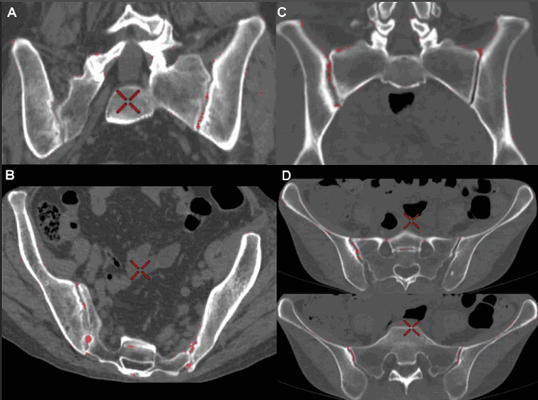

Для определения достоверного сакроилеита по МРТ необходимо наличие околосуставной зоны отека костного мозга одной анатомической области не менее, чем на двух последовательных срезах, или наличие зоны отека костного мозга двух и более анатомических областей хотя бы на одном срезе.

На рисунке – слева в теле подвздошной кости и боковой массе крестца обширные зоны отека костного мозга, явления инфильтрации окружающих мягких тканей

МР-картина патологического кистозно-солидного образования (хордомы) на уровне дистальных отделов крестца и копчика (стрелка)